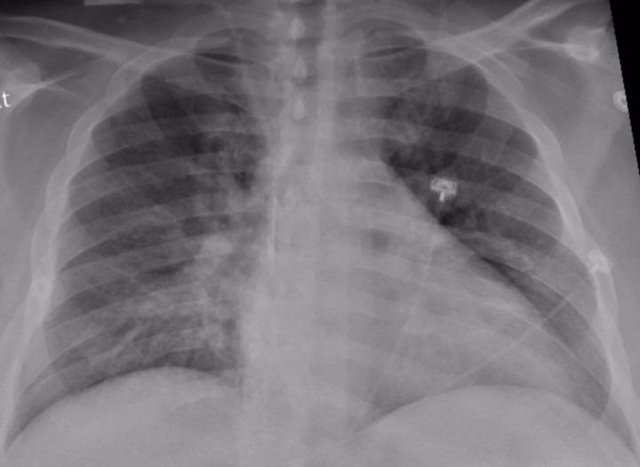

El estudio, dirigido por el neumólogo Bram van den Borst, incluyó a 124 pacientes que se habían recuperado de infecciones agudas por COVID-19. Visitaron la clínica de cuidados posteriores corona del centro médico de la universidad de Radboud, en Países Bajos. Los pacientes fueron examinados por tomografía computarizada y una prueba de función pulmonar, entre otros análisis.

Después de tres meses, los investigadores hicieron un balance, que reveló que el tejido pulmonar de los pacientes se estaba recuperando bien. El daño residual en el tejido pulmonar fue generalmente limitado y se observa con mayor frecuencia en pacientes que fueron tratados en la UCI.

El investigador principal y neumólogo Bram van den Borst explica: «Los patrones que vemos en estos pacientes muestran similitudes con la recuperación después de una neumonía aguda o síndrome de dificultad respiratoria aguda (SDRA), en el que se acumula líquido en los pulmones durante mucho tiempo. Es alentador ver que los pulmones después de las infecciones por COVID-19 exhiben este nivel de recuperación», apostilla.